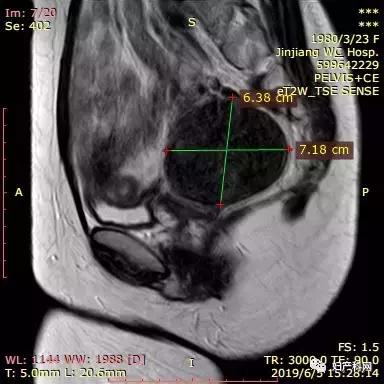

2005年和2013年腹腔镜卵巢囊肿手术各一次,病理均为子宫内膜异位囊肿,3年前复诊时发现子宫肌瘤,同时发现卵巢囊肿术后复发,均未做治疗,现因自觉小便次数多,贫血就诊。在2005年和2013年两次手术时医生均提到“腹茧症”。平素月经:7-10天/26-30天,痛经(-),量偏多,用1-2包卫生巾。MRI(2019.6.6):1、子宫颈肌瘤5.2*6.2*6.9cm。2、子宫前方囊性占位4.1*4.9*6.6cm,倾向良性。宫颈刮片(2019.4):正常。2019年4月HB 94g/L

我们给这位客人选择的治疗方式为经皮卵巢囊肿穿刺+无水酒精固化+经皮子宫肌瘤微波消融术。术中从右侧卵巢囊肿内抽出褐色液体约70ml,使用无水酒精20ml固化15分钟后抽出。子宫肌瘤原本预计经阴道穿刺,但因为子宫肌瘤位置较偏,阴道穿刺后评估安全性存在问题,改为了经皮穿刺,60w功率下消融了18分30秒,子宫肌瘤基本达到完全消融。